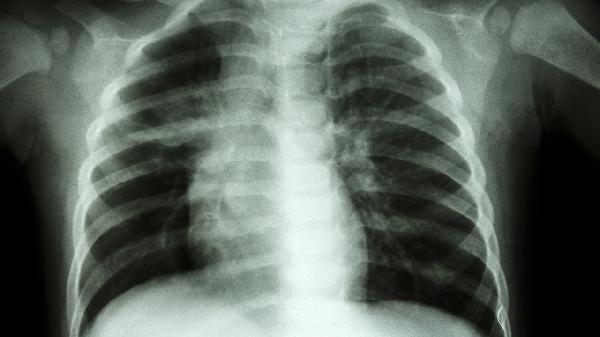

4、胸部X線片

胸部X線片可間接反映二尖瓣畸形引起的繼發(fā)改變。典型表現(xiàn)包括左心房擴大、肺靜脈充血等征象,嚴重者可見KerleyB線等肺水腫表現(xiàn)。該檢查操作簡便但特異性較低,不能直接顯示瓣膜結(jié)構(gòu)。孕婦應避免此項檢查,兒童需做好防護措施。